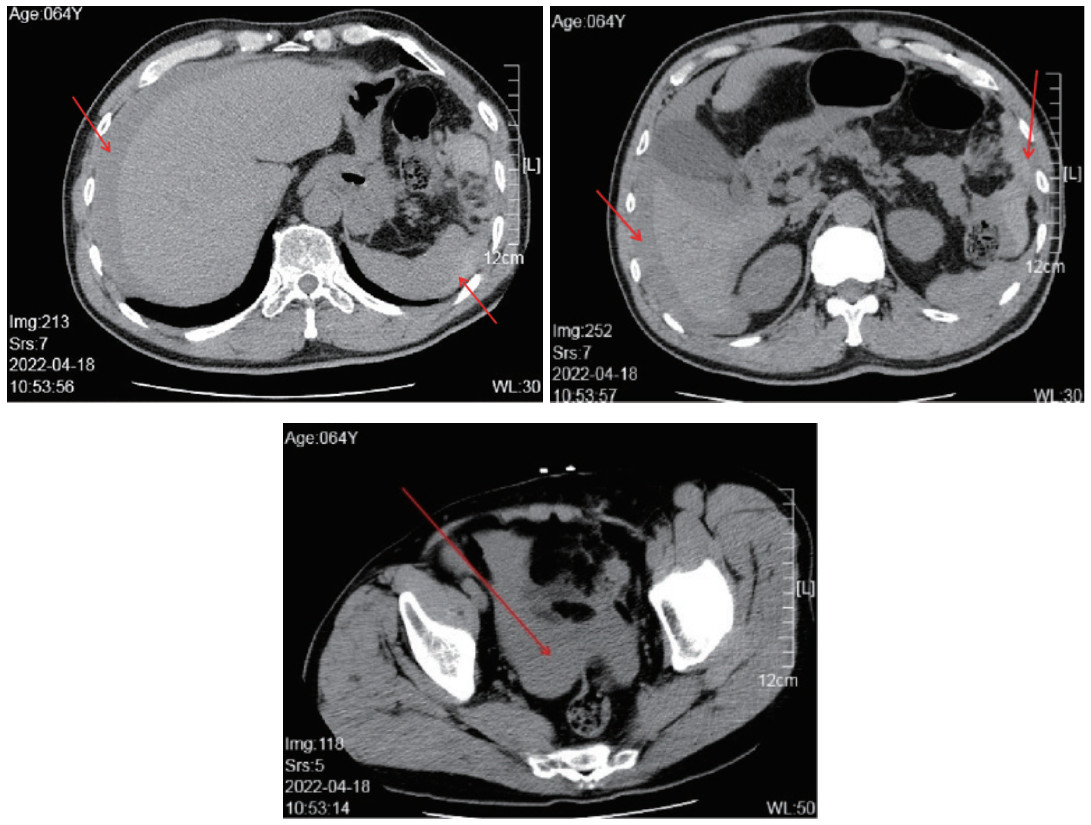

1 资料与方法患者,男,64岁。因“腹痛、腹胀2 h,晕厥后0.5 h”就诊。现病史:患者约2 h前无明显诱因出现腹痛、腹胀,疼痛以中上腹为主,伴恶心,无呕吐、腹泻、心慌、胸闷、胸痛、大汗或发热;0.5 h前上厕所起身时突发晕厥倒地,未见抽搐、呕吐、二便失禁;上厕所时患者并未解出大便,患者和家属明确否认外伤情况;数秒后患者恢复神志,意识清楚,无逆行性遗忘,无头晕、头痛、心慌、胸痛等不适,仍有腹痛,疼痛与之前程度相似;随后不久在行走时再发晕厥一次,亦为数秒后恢复神志,否认外伤情况;家属遂拨打120,由120转运到达急诊科就诊。补充病史,患者近2 d大便未解,发病前1日有饮酒,睡眠差。患者既往有慢性胃炎,便秘病史;否认高血压、心脏病、糖尿病等慢性病史;否认肝炎等传染病史;否认食物药物过敏史。入急诊科后,直接送入抢救室,初步体格检查:T 36.1℃,P 94次/min,R 19次/min,BP 105/70 mmHg,SP02 96%,神清,言语清晰,急性痛苦面容,双瞳孔等大等圆,直径3 mm,光反射存在,伸舌居中,无贫血貌,强迫体位,HR 94次/min,心律齐,双肺呼吸音清晰,等称,未闻及明显干湿啰音,腹部稍膨隆,腹肌稍紧张,全腹部压痛,以左上腹最为明显,反跳痛可疑阳性,肠鸣音减弱,双肾区无叩击痛,双下肢不肿,四肢肌力肌张力正常,双侧病理征未引出;全身未见开放性外伤征象。在抢救室,给患者进行了心电、血压、血氧饱和度监测,卧床休息,建立静脉通道;安排了心电图、血常规、肌钙蛋白、凝血象-D二聚体、肝肾功能电解质、淀粉酶,以及CT平扫检查(颅脑+胸部+腹盆);与患者家属充分沟通病情;等待查血结果的过程中,给予患者解痉治疗,并动态观察病情变化。心电图未见明显异常;首先回报的查血结果提示WBC 18.08 109/L,N 14.95 109/L,NEUT 82.70 %,红细胞、血红蛋白、血小板均在正常范围内;肌钙蛋白正常;等待其他查血结果期间,患者从影像科返回抢救室,立刻连线影像系统初步阅片,发现肝周积液(积血?),脾脏及脾周见密度不均匀表现,左中腹部混杂密度表现,盆腔积液(积血?)(图 1)。立刻联系胃肠外科、肝胆外科急会诊,联系影像科急诊报告,并启动急诊手术术前准备,开放第二条静脉通路给予补液。影像报告提示:左中腹部、脾周及左结肠旁沟血肿,不除外肠系膜血管出血或脾破裂?腹腔及盆腔积液。专科床旁会诊后,考虑初步诊断为腹腔积血原因待查;肠系膜血管损伤?;脾破裂待排。期间查血结果回报:D-二聚体升高0.94 mg/L(升高),纤维蛋白原1.55 g/L;淀粉酶正常;其他生化结果和电解质基本正常。护送患者前往手术室行急诊手术,中上腹部正中切口行剖腹探查术,术中见腹腔内大量红色不凝血液及部分血凝块,清除积血及血凝块,量约2 000 mL,发现靠近胰尾部大网膜出血血肿,探查腹腔其他脏器未见出血,行大网膜病损(血肿)切除术,术中观察切除病灶没有发现有恶性肿瘤或动脉瘤的依据;术后温盐水反复冲洗腹盆腔,检查无出血后,脾窝放置引流管一根。术后安返ICU,予以重症监护,维持水盐平衡,抗感染,抑酸护胃、营养支持等对症支持治疗。患者于术后第2天复查胸腹CT,提示:慢支、肺气肿;双肺多发TB纤维化及硬结钙化增殖灶;双侧胸腔及腹腔少许积液;腹膜出血治疗后改变,双肾囊肿,右输尿管下段结石;腹部肠腔明显扩张、积气,多发气液平,考虑肠梗阻。患者症状体现为腹胀、炎症水平较高,治疗上较前增加扩肛、胃管注入石蜡油、开塞露通便、小茴香热敷等对症处理。术后第3天转回普通病房,给予心电监护、吸氧、动态监测血压及指脉氧、监测血糖、抗感染、雾化祛痰、护胃、抑酶、补充白蛋白、营养支持、小茴香热敷腹部、口服石蜡油、人工扩肛、开塞露刺激直肠、超声药物透入治疗、切口换药、理疗等支持对症治疗。术后第4天病理回报:送检(大网膜)脂肪组织局部出血伴血肿形成。术后12 d复查腹部CT:腹膜出血治疗后改变,腹膜增厚;双肾多发囊肿;腹部肠腔扩张、积气;双侧少许胸膜反应。患者术后13 d拆线、拔管出院。术后3个月随访患者,自诉感觉良好,没有再出现类似症状。

| 图 1 腹部CT(横切面)图像,箭头所示为腹腔/盆腔积血 |